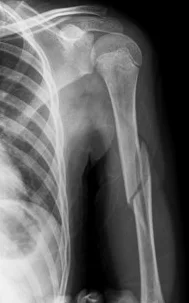

Humeral Shaft Fracture

- Possible associated injury to The Radial nerve (why?)(signs?)

Humeral Shaft Fracture- Management

- Conservative: U-shape slab) / splint / orthosis

- Gravity maintains reduction

- Management:

- Operative: (plate or IMN)

- Indications:

- Sever displaced Unreduced,

- Bilateral,

- multiple injuries

- floating elbow,

- Needs to use crutches

- Patients’ preference (active, athlete)